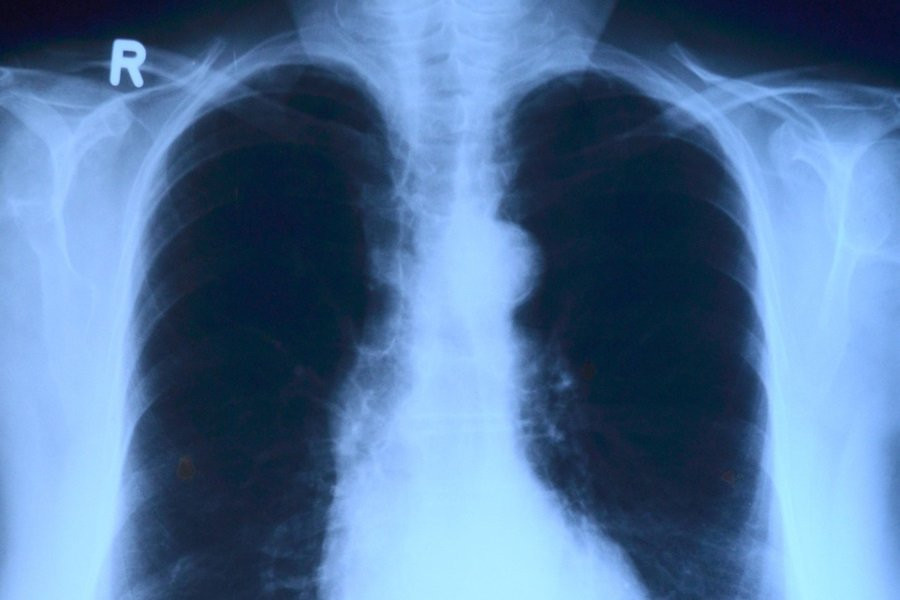

"Известия": В России разработан препарат уничтожающий рак легкого светом

Учёные НИТУ МИСиС и Национального медицинского исследовательского центра онкологии разработали новый препарат, который может помочь в лечении рака. Он основан на использовании особых бактерий, которые получают энергию от солнечного света и содержат вещество под названием бактериохлорин, пишут "Известия".